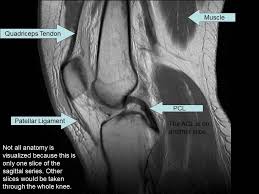

These muscles work in groups to flex, extend and stabilize the knee joint. Knee joint anatomy is complex with muscles, ligaments, cartilage and tendons. Magnetic resonance imaging is particularly well suited for the medical evaluation of the musculoskeletal (msk) system including the knee, shoulder, ankle, wrist and elbow. 1 november 2002 mri anatomy of the knee and shoulder james y. The muscles of the knee include the quadriceps, hamstrings, and the muscles of the calf. Three conventional mri planes that are utilized to evaluate the knee include sagittal (oblique), coronal, and transaxial planes. There is a flat area of tendon originating from the knee. In this presentation mri anatomy biceps femoris muscle. Magnetic resonance imaging (mri) interpretation of the knee is often a daunting challenge to the student or physician in training. The knee joins the thigh bone (femur) to the shin bone (tibia). Injuries such as anterior cruciate ligament, meniscus and rotator cuff tears are all easily diagnosed when there is a firm understanding and knowledge of human anatomy. These motions of the knee allow the body to perform such important movements as walking, running, kicking, and jumping. Song, uc san francisco msiv gillian lieberman md.

This mri knee sagittal cross sectional anatomy tool is absolutely free to use. It is considered a vestigial muscle, and can be used as a tendon graft in reconstructive orthopedic surgery. They are attached to the femur (thighbone), tibia (shinbone), and fibula (calf bone) by fibrous tissues called ligaments. Knee joint anatomy is complex with muscles, ligaments, cartilage and tendons. These motions of the knee allow the body to perform such important movements as walking, running, kicking, and jumping. Magnetic resonance imaging is particularly well suited for the medical evaluation of the musculoskeletal (msk) system including the knee, shoulder, ankle, wrist and elbow. These muscles work in groups to flex, extend and stabilize the knee joint. Plantaris can have variable size, but in most cases is difficult to demonstrate on routine mri studies. Injuries such as anterior cruciate ligament, meniscus and rotator cuff tears are all easily diagnosed when there is a firm understanding and knowledge of human anatomy. When a muscle has different orientations of the tendons it means that there are different patterns of edema possible depending on the tendon injured. Song, uc san francisco msiv gillian lieberman md. Three conventional mri planes that are utilized to evaluate the knee include sagittal (oblique), coronal, and transaxial planes. Mri knee anatomy knee sagittal anatomy free cross sectional anatomy mri knee mri diagnostic imaging :

Abnormal anatomy with normal signal, i.e. It is the largest synovial joint in the body and allows flexion and extension of the leg as well as some rotation in the flexed position. Anatomical structures of the lower limb (hip, thigh, knee, leg, ankle and foot) and specific regions (compartment of the lower. The muscles of the knee include the quadriceps, hamstrings, and the muscles of the calf. Mri knee anatomy scroll using the mouse wheel or the arrows. In this presentation mri anatomy biceps femoris muscle. Knee anatomy the orthopedic sports medicine institute in they act like strong ropes to connect bones. Three conventional mri planes that are utilized to evaluate the knee include sagittal (oblique), coronal, and transaxial planes. T2w axial fat sat 1. 1 november 2002 mri anatomy of the knee and shoulder james y. Louis, usa and the rijnland hospital in leiderdorp, the netherlands. Injuries such as anterior cruciate ligament, meniscus and rotator cuff tears are all easily diagnosed when there is a firm understanding and knowledge of human anatomy. Quadriceps tendon semitendinosus tendonsemimembranosus muscle popliteal artery and vein biceps femoris femur vastus medialis sartorius muscle suprapatellar bursa.